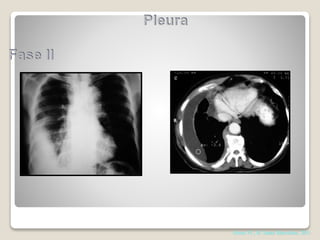

Fases

1-EXSUDATIVA NÃO COMPLICADO

2 FIBRINO-PURULENTA

3 ORGANIZAÇÃO

COMPLICADO

Shields. Thoracic Surgery,Clinics 7 edition; 2015

Diagnóstico: derrame pleural

parapneumônico ou empiema – Fase 2

Nestes casos é possível que

toracocentese não tenha sucesso